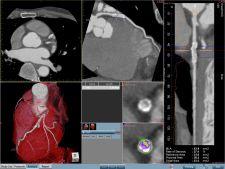

Providing a full suite of advanced 3D analysis tools, Ziostation is based on thin-client architecture that requires no proprietary or specialized hardware components. It also does not necessitate a separate standalone workstation to supplement its functionality. The Ziostation is reportedly highly scalable with unified architecture including the ability to load-balance case processing. It also features a customizable user interface and action macros to maximize efficiency across various user types.

Clinical toolset include:

- CT coronary analysis

- CT cardiac function analysis

- CT calcification scoring

- CT advanced vessel analysis